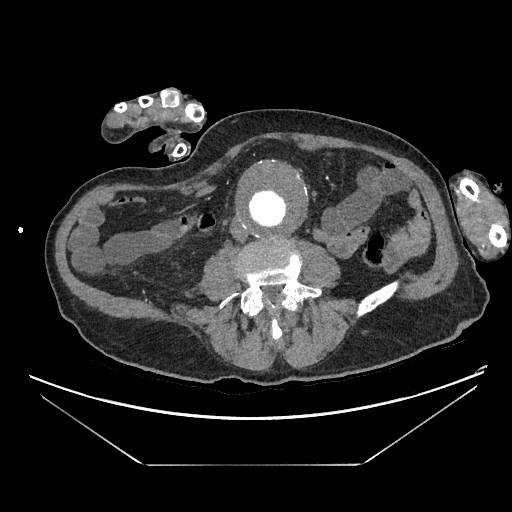

Dados los hallazgos, se completa estudio con AngioTC, confirmando la existencia de aneurisma infrarrenal de 6 mm de diámetro mayor, junto con litiasis renal derecha de 5,5 mm y dilatación de la pelvis renal.